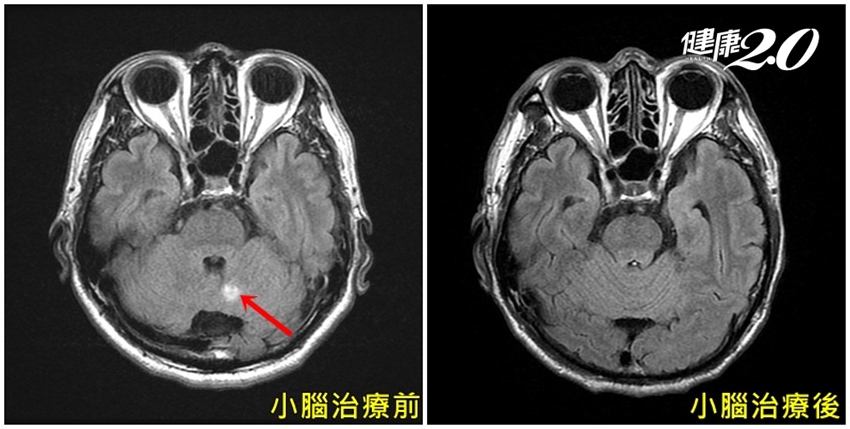

▲▼由照片 中可明顯看余先生經過「好神刀」治療後,腦部腫瘤已消失 。

考量余先生已有多重轉移,雖然腦瘤約1公分,但分別位於大腦及小腦,加上身體狀況並不適合手術治療,與患者溝通後,選擇接受「好神刀」(Halcyon)放射治療,追蹤治療效果十分正面,讓患者與醫療團隊都感到非常振奮。

余先生經連續治療10天後,追蹤磁振掃描影像檢查顯示腦部腫瘤已完全消失,頭暈症狀也大幅改善,步態恢復正常,讓家人寬心不已,笑說:「終於不會再打醉拳了」。